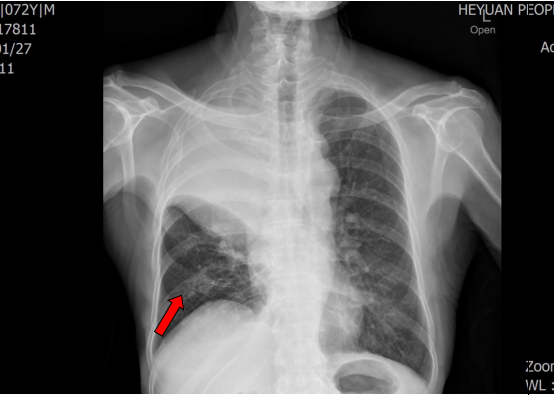

胸片(术前):右肺上叶中央型肺癌并右肺中下叶阻塞性肺不张

经过术前充分准备,罗少华主任带领气管镜室团队在表面麻醉下为患者行经支气管镜激光消融术,气管镜下见右中间支气管新生物堵塞管腔,行激光消融,仅半个小时就清除了管腔内大部分肿瘤组织,手术实施过程顺利,右中间支气管恢复畅通。术后患者呼吸困难明显缓解,复查胸片右中下肺叶复张,患者恢复良好,已出院。

胸片(术后):右中下肺叶复张